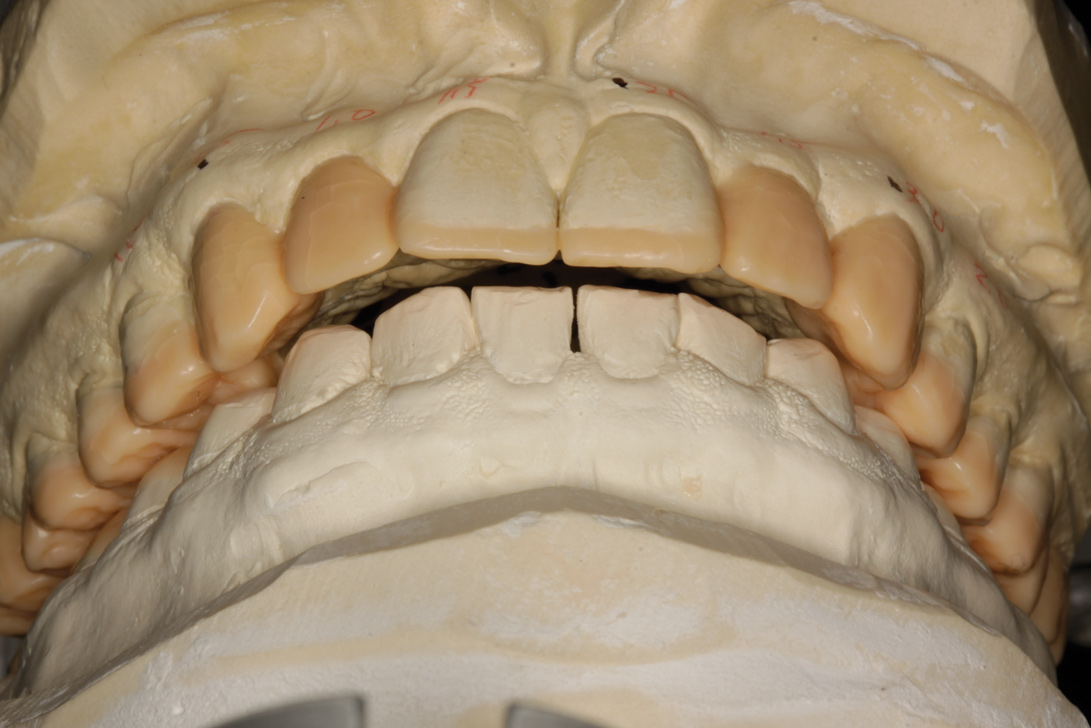

Fig 7. Complete diagnostic wax-up mounted in fully seated joint position. Note the Class II malocclusion unveiled once vertical dimension was restored and tooth proportions re-established. Horizontal overlap is excessive and can be overcome either by orthodontic camouflage, overcontoured prosthodontics, or moving teeth facially into augmented bone via SFOT. The latter approach allows for more ideal tooth positioning and minimally invasive dentistry.

Figure 7